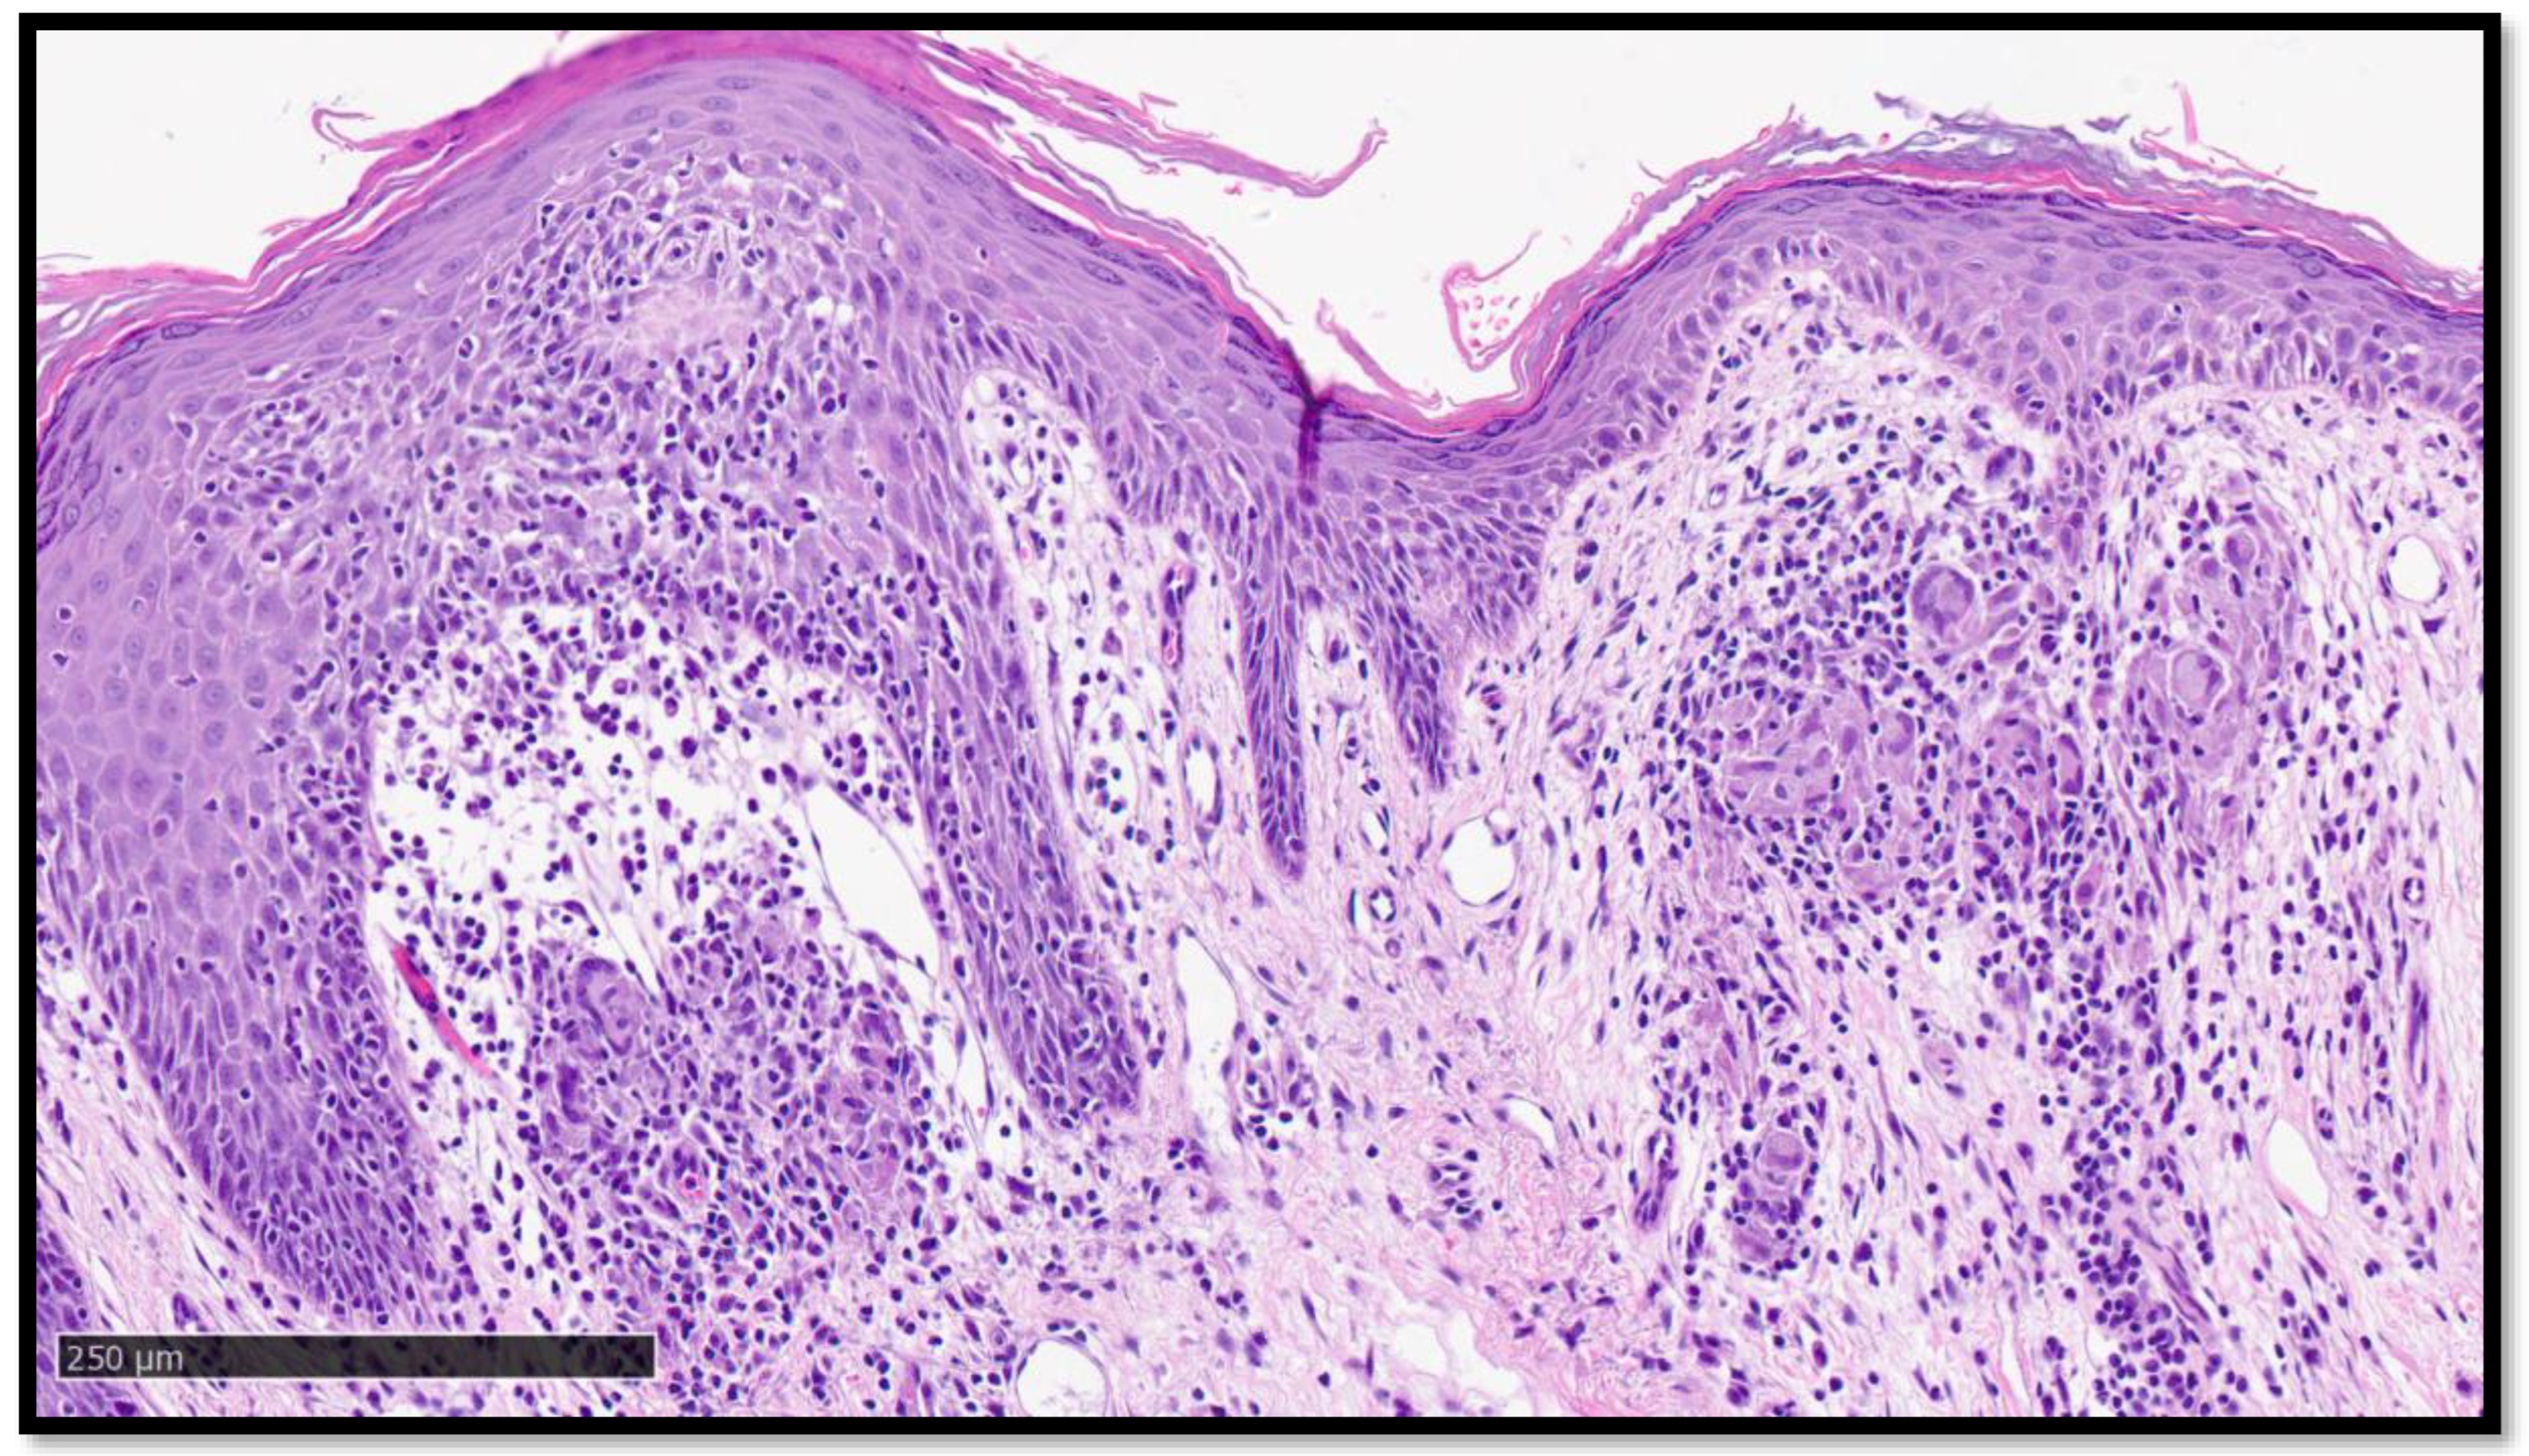

Cutaneous Sarcoidosis-like Eruption Following Second Dose of Moderna mRNA-1273 Vaccine: Case or Relationship?

Cazzato, G.; Ambrogio, F.; Foti, C.; Capuzzolo, M.; Trilli, I.; Casatta, N.; Lupo, C.; Carrieri, M.; Daini, D.; Colagrande, A.; et al. Cutaneous Sarcoidosis-like Eruption Following Second Dose of Moderna mRNA-1273 Vaccine: Case or Relationship? Diagnostics 2023, 13, 1286. https://doi.org/10.3390/diagnostics13071286